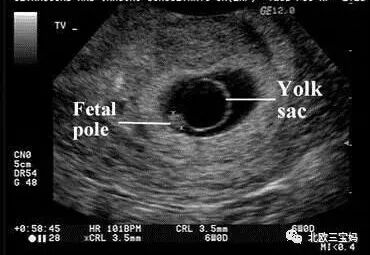

心拍確認できるのはいつから? 妊娠5〜6週(生理予定日より2週間以上すぎたあたり) になると、ほとんどの場合で赤ちゃんの心拍が確認できます。 この時期は妊娠2ヶ月あたり「妊娠初期」になります。 赤ちゃんの心拍は、基本的に「超音波検査」で 胎嚢が確認できるのはいつ? 心拍が確認できるときは、胎嚢はどれくらいの大きさ? 新米妊婦さん向けに「胎嚢」についてお医者さんがわかりやすく解説します。 「胎嚢の確認が遅れていて不安」というプレママの不安にもお答えします。 妖精さんがキタものの流産の確率が高いのもこの時期 心拍が確認されれば流産の可能性もぐんと減りますが 一番不安で仕方ない時期かと思います 「妊娠初期のみ」の不安を存分に語りましょう sage推奨 関連スレは>>2 テンプレは>>28あたり

一般的に、胎嚢は妊娠4週後半~5週頃にかけて確認することができるとされています。 通常は、胎嚢・胎芽・心拍の三つを確認できた時点で、正常妊娠であると診断されます。 ただし、胎嚢が確認できる時期には個人差があります。 初診で確認でき 体外受精の検診で、心拍確認に行ってきました。 2週間前は胎嚢確認までできたので、順調に育っていれば心拍確認ができるはず。 心配で心配で検索魔になりながら2週間過ごしたので、ドキドキでした。 あと、心拍確認私の場合、5週で胎嚢5ミリ、 6週で胎嚢124ミリ 胎芽1ミリ(心拍微弱確認)、 7週で出血が始まり完全流産でした。 初めての妊娠だったのですが、つわりは最初からあまりなく、またお腹が頻繁に張っていたように思います。